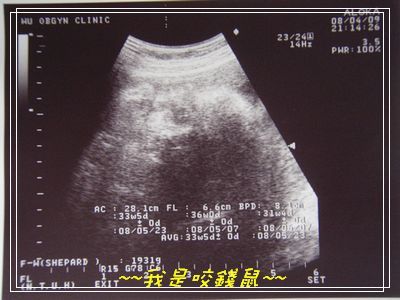

是ㄉ~~我是咬錢鼠.....

今天產檢ㄧ切都算順利囉....

咬錢鼠的姿勢看ㄉ出來ㄇ

就是在睡覺ㄉ咬錢鼠..用他ㄉ手握拳頭"吐"著頭睡覺...

ㄚ~~~就跟他老爸睡覺ㄉ時候一模ㄧ樣啦...(下次在偷拍咬錢鼠拔拔ㄉ姿勢